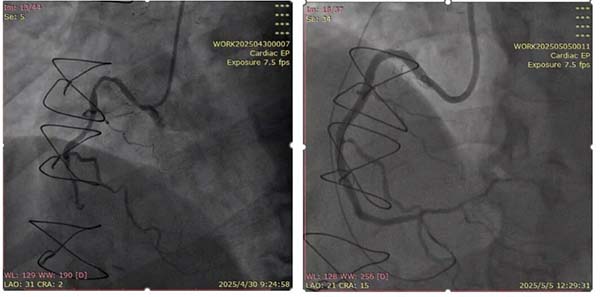

术前造影提示RCA-CTO(左)RCA开通后血流恢复(右)